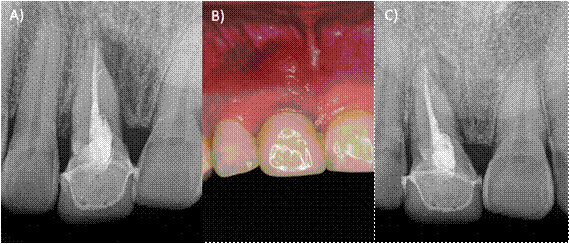

A la exploración clínica observamos una tumefacción de los tejidos en la zona anterosuperior y presencia de tracto sinusal, una restauración desajustada correspondiente a una corona libre de metal, invasión del espesor biológico, inflamación gingival, dolor a la masticación, percusión horizontal y vertical (Fig. 1B). En la radiografía periapical del órgano dental #11 (orto-radial y mesio- radial) observamos lesión radiolúcida en la raíz a nivel apical y mesial, perdida de la cresta ósea interproximal y lamina dura no visible. En la porción apical observamos una subobturación (Fig. A,C). Se realizó una TCHC y al observar la tomografía se confirmó la presencia de dos raíces en dicho órgano dentario de las cuales, solo la raíz vestibular estaba tratada endodónticamente (Fig. 2 A-B). Diagnóstico: Órgano dental previamente tratado con absceso apical crónico29. Se anestesio con articaína 4% con epinefrina 1:100 000 supraperióstica en fondo de saco anestesiando el nervio alveolar anterior, se eliminó la restauración coronaria utilizando una fresa de diamante y pieza de mano de alta velocidad, una vez retirada, se realizó aislamiento absoluto con dique de goma, se procedió a eliminar la gutapercha con limas Wave One Gold (Dentsply Sirona, Tulsa Dental), se exploró el conducto palatino con limas tipo K 6 y 8 hasta lograr permeabilizarlo, la longitud de trabajo de ambas raíces se obtuvo con la ayuda de localizador apical Apex ID (SybronEndo, Orange, CA)(Fig.3A), se instrumentó con limas Wave One Gold (Dentsply Sirona, Ballaigues, Switzerland ) Large (45/05) para el conducto vestibular y médium (35/06) para el conducto palatino, la irrigación se realizó con hipoclorito al 5.25 % durante todo el tratamiento para finalizar con un protocolo de irrigación de 3 ciclos de 20 segundos, hipoclorito de sodio 5.25%, agua destilada y EDTA 17% (Smear clear Sybron Endo, CA), activados con ultrasonido (Ultra X, Eighteeth Medical), se colocó hidróxido de calcio como medicación intraconducto durante 15 días. La segunda cita se realizó nuevamente protocolo de irrigación, los conductos se secaron con puntas de papel estériles y fueron obturados con técnica de onda continua de calor (Fast fill and Fast Pack, Eighteeth Medical) y cemento AH-Plus (Dentsply Maillefer, Ballaigues, Switzerland) (Fig. 3 B-C), por último, se utilizó resina fluida para el sellado del acceso coronal. Se solicitó una segunda TCHC para evaluar la correcta localización y obturación del órgano dental (Fig. 4 A-B).

Figura 1: A) Radiografía preoperatoria orto-radial. B) Fotografía clínica preoperatoria, se observa aumento de volumen y cambio de coloración. C) Radiografía preoperatoria mesio-radial.